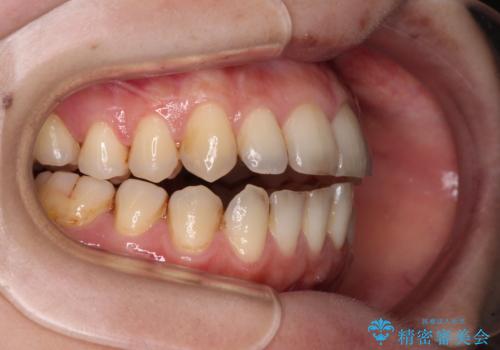

- 上下前歯の隙間を気にして来院された患者様です。

下顎前歯が1本欠損しており、上下小臼歯はクロスバイトとなり、上下前歯の接触もないという不正咬合の状態でした。

クロスバイトはワイヤー矯正が得意とするところであり、上下前歯の非接触や開咬はインビザラインの得意とするところであるので、ワイヤー装置により事前にクロスバイトを改善し、その後にインビザラインにて仕上げていくこととしました。